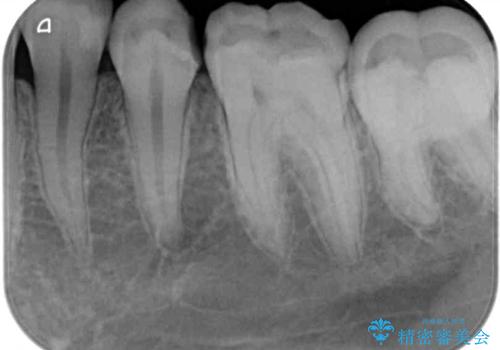

- 以前治療した詰め物が欠けてしまったことを主訴として来院した患者様です。

食べ物がはさまったり、冷たいものがしみるといった症状がみられました。

むし歯の染め出し液と拡大鏡を用いて、むし歯がないことを確認し、

セラミックインレーにて修復することとしました。